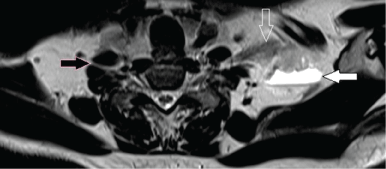

| Figure 6: A 68-year-old male with intraneural synovial sarcoma of BP. Axial T2-weighted MR image shows a mass arising from the left C7 nerve root (open arrow) with central fluid-fluid level (solid arrow). Note the normal right C7 spinal root (black arrow) in between the anterior and middle scalene muscles. | ||